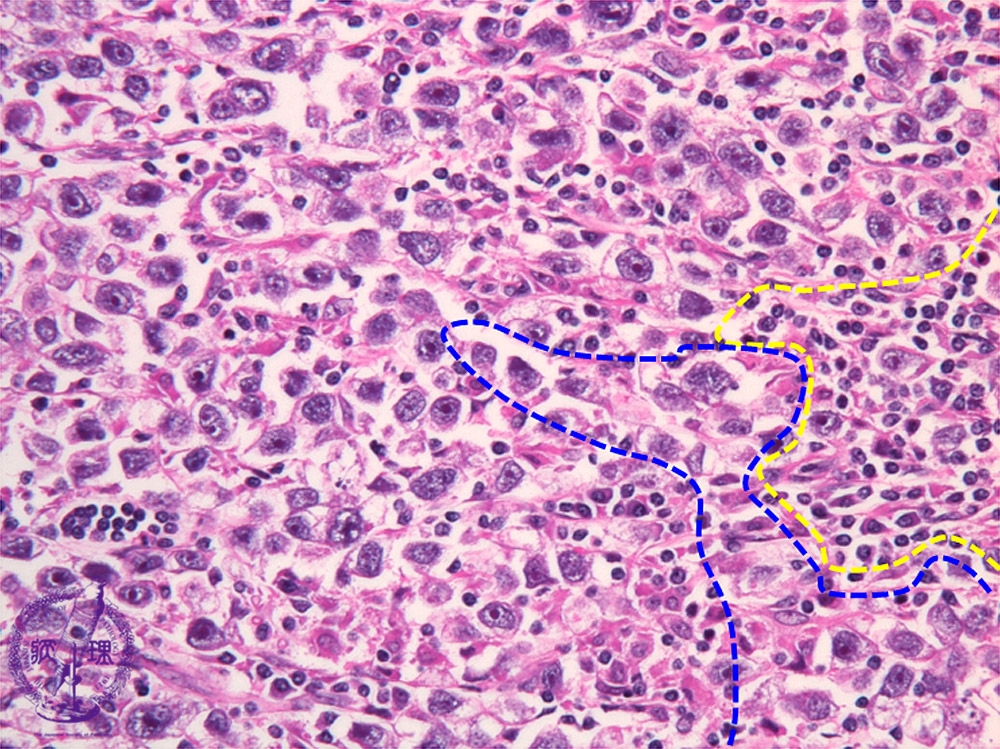

Histology (HE stain, high power): Seminoma. Tumor cells have rounded nuclei with coarse chromatin and 1 or 2 distinct nucleoli. Mature lymphoid cell infiltration results in two cell pattern with tumor cells (tumor cells: blue dotted line, lymphoid cells: yellow dotted line).